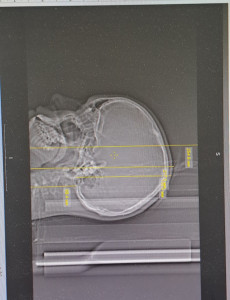

Ребенку тольтко 13 лет исполнилось сделали кт головы, как врач сказал, но оказалось там все обоучили и голову и лиц скелет и шею L=25см. DLP 752 CTDI 30мГр. Пересчет в эф.дозу сделали коэфициентом для головы, а не общим голова/шея, чтоб снизить дозу. Как потом оказалось на всякий случай. Шею облучали дозой для головы 30 мГр, хотя для шеи она в 3 раза ниже должна быть. Какое для нас это горе не передать словами. Прошу подсказать 1)сколько шейных позвонков вошло в зону облучения2) попала ли щитовидка и какое облучерие она получила даже рассеивающее, защиту не надевали 3) гортань, слюные железы также облучили дозой выше нормы для костей 4) подскажите про расчет SSDR реально поглощенная доза по диаметру головы, если фантом 16 см, а головы больше диаметром эффектианым, то реалтно рогл.доза меньше CTDI, а для шеи? Ведь у нее диаметр меньше, значит она еще больше 30 мГр поглотила? 5) какая дрза облучени косного мозга получилась от облучерия головы и шеи? 6) по кт снимкам поле fov 25 см, а анатомическая область 23 см от низа до макушки. Над голоаой 2 см пустоты, куда делось облучение по спирали,прошедшее в пустоте над головой? 7) про дополнительные ротации в начале и в конце облучения. Это значит CTFIx2=60мГр в начале и в конце??? 7)какими анализами сейчас контролировать последствия, научные статьи подтверждают факт ужасного влияния кт. Голова от кучи вопросов разрывается. В больнице говорят- так получилось.